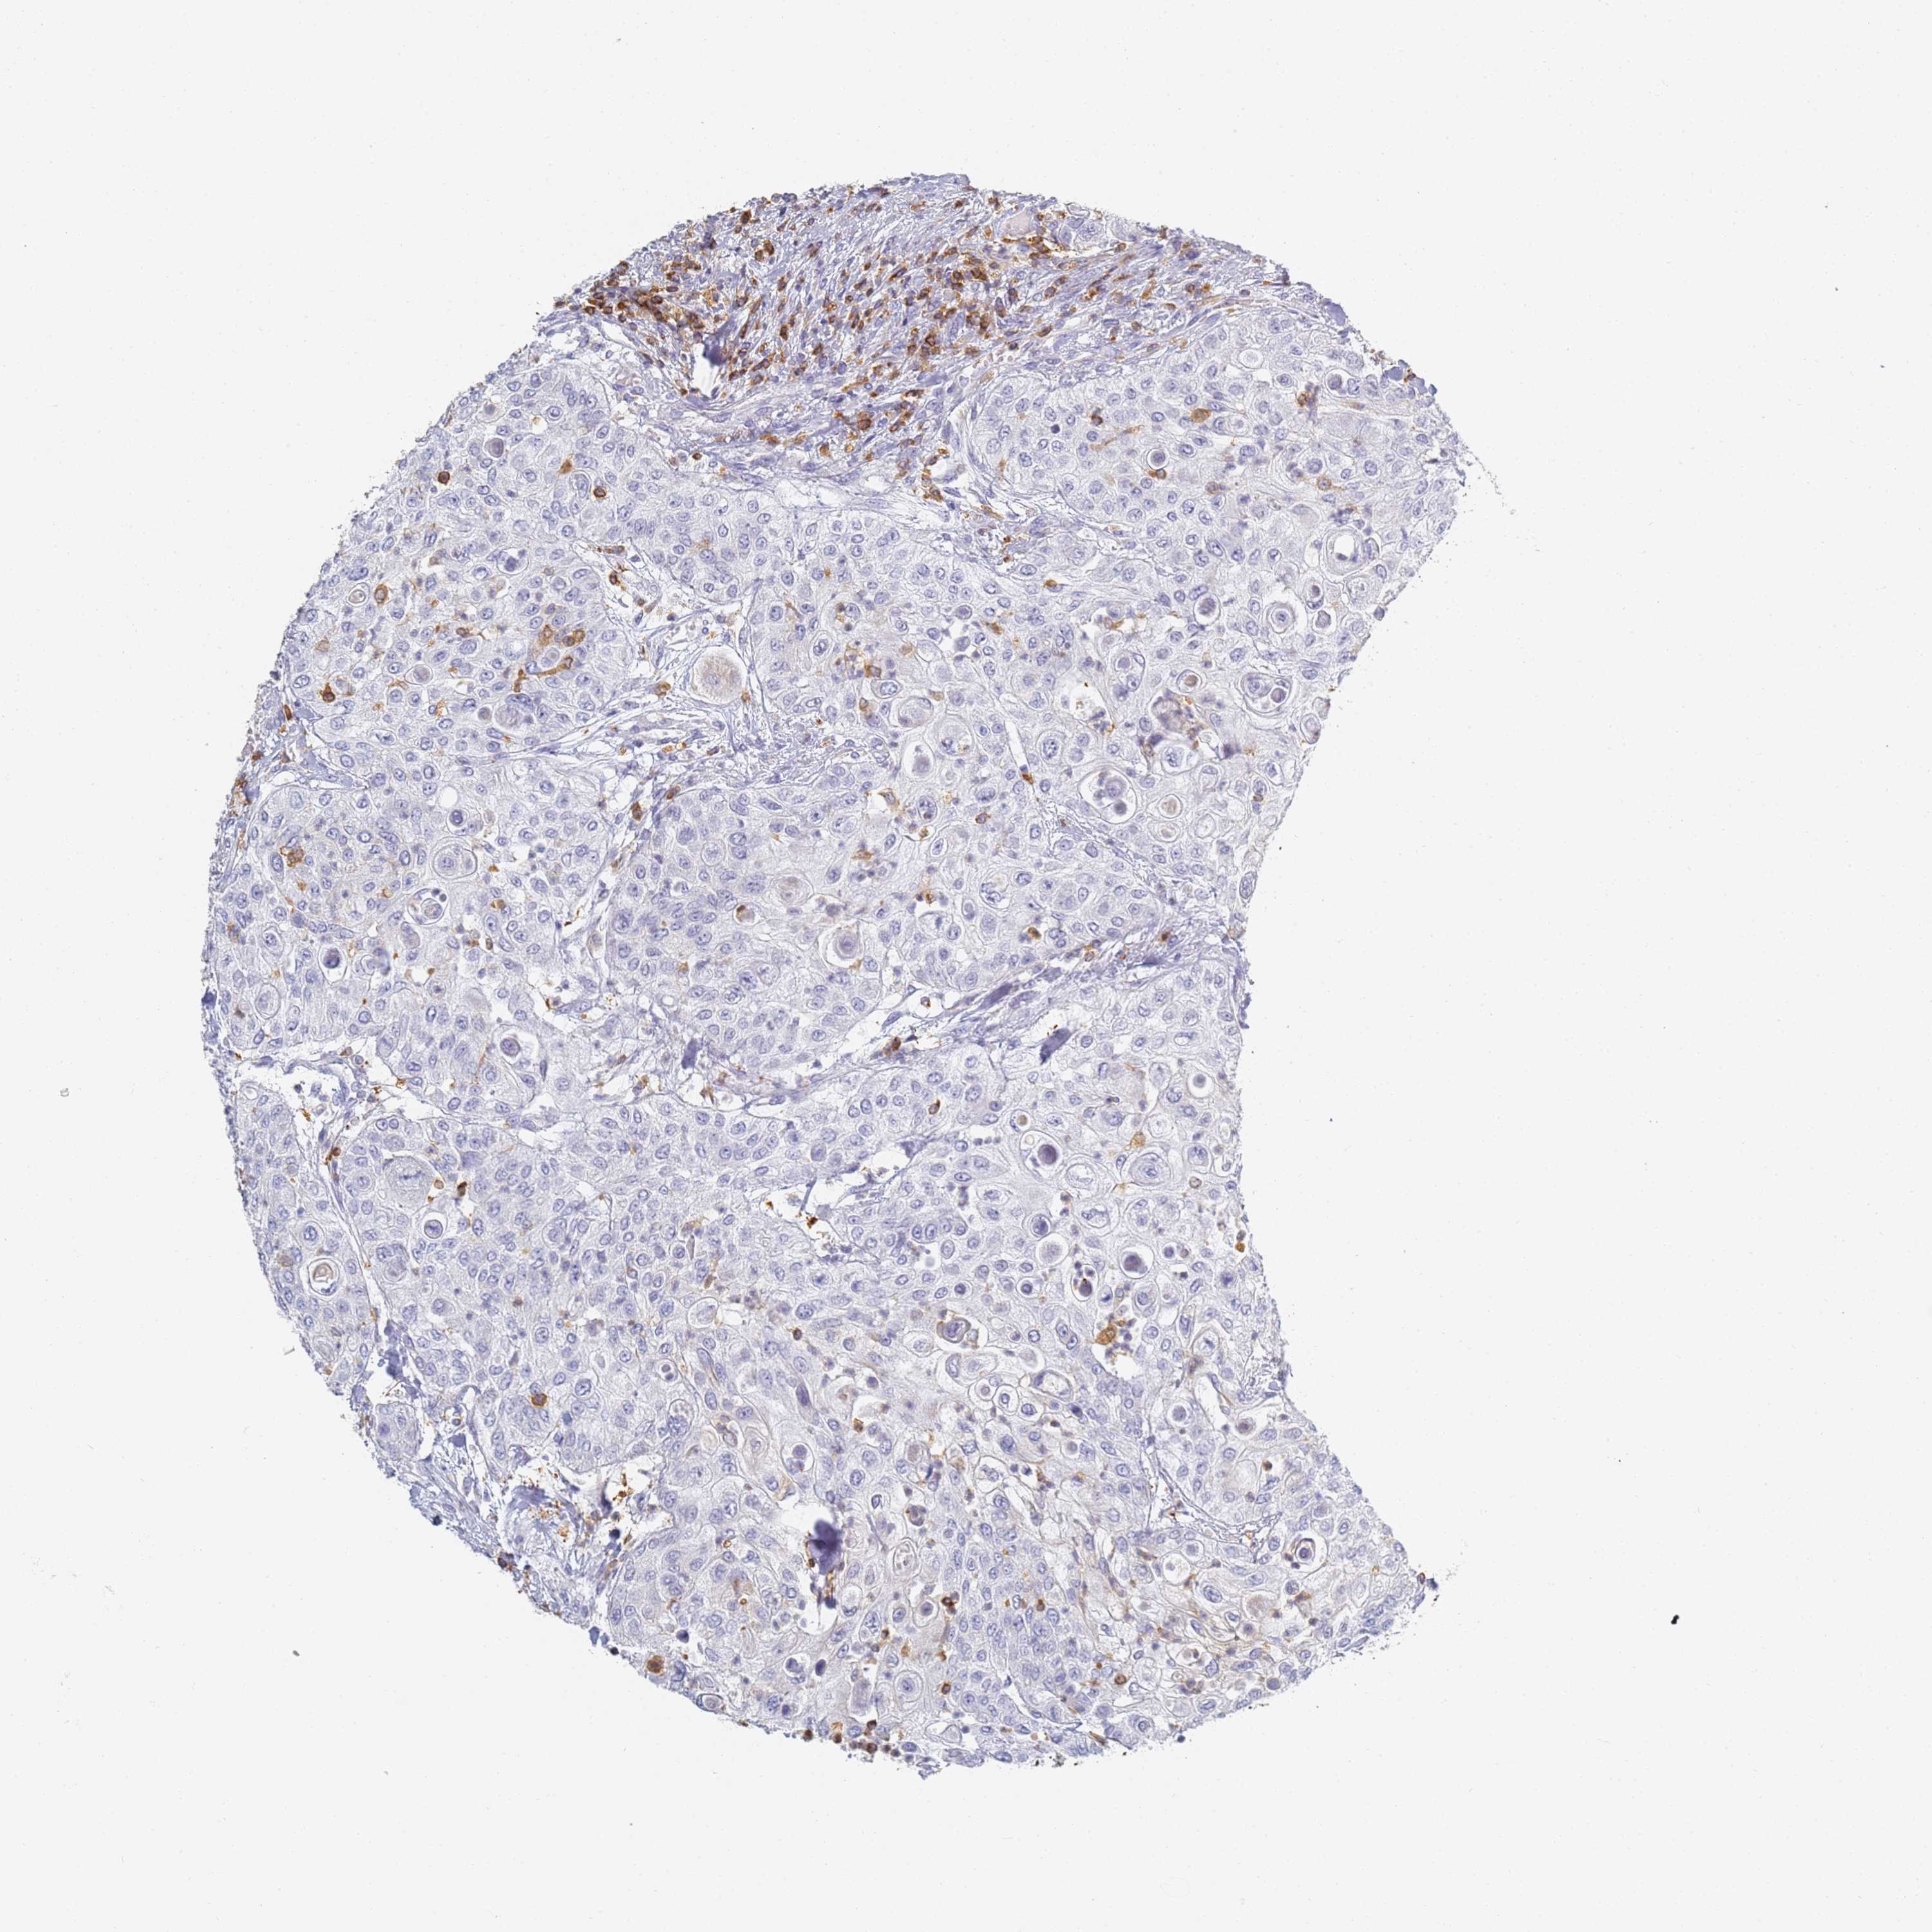

UROTHELIAL CANCER - Protein expressioni

A mouse-over function shows sample information and annotation data. Click on an image to view it in a full screen mode. Samples can be filtered based on level of antibody staining by selecting one or several of the following categories: high, medium, low and not detected. The assay and annotation is described here.

Note that samples used for immunohistochemistry by the Human Protein Atlas do not correspond to samples in the TCGA dataset.

Antibody stainingi

Antibody staining in the annotated cell types in the current human tissue is reported as not detected, low, medium, or high, based on conventional immunohistochemistry profiling in selected tissues. This score is based on the combination of the staining intensity and fraction of stained cells.

Each image is clickable and will lead to virtual microscopy that enables deeper exploration of all samples and also displays staining intensity scores, fraction scores and subcellular localization as well as patient and tissue information for each sample.

Antibody HPA038666

Antibody HPA038667

Urothelial carcinoma, High grade

Urothelial carcinoma, Low grade